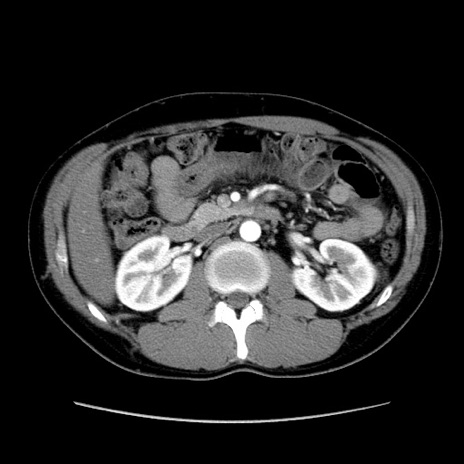

症例36(横断像)

【症例】20歳代 男性

【主訴】心窩部痛

【現病歴】今朝より上腹部痛あり。一旦軽快していたが再度出現したため救急要請。昨日夕に白身の魚を含む刺身を食べた。

【身体所見】BP 136/89mmHg、HR 74/min、BT 37.0℃、腹部:膨満、軟、心窩部に圧痛あり。反跳痛なし、筋性防御なし、腸雑音やや亢進あり。

【データ】WBC 17700、CRP 0.48